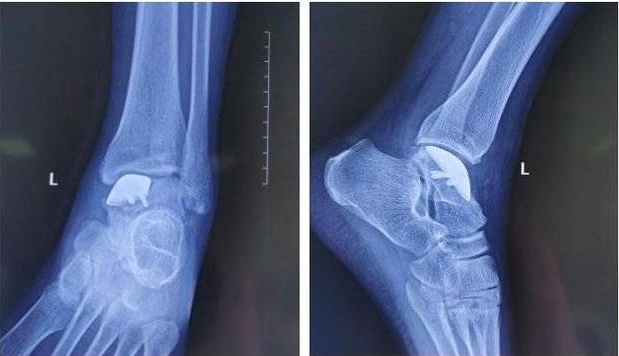

△術(shù)后X線情況